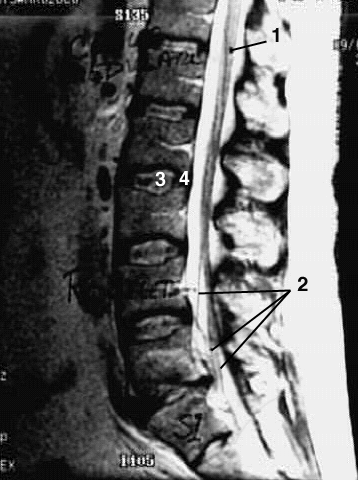

Radiology Images

Back- Lumbar Spine Zoom 1

1. Conus Medullaris

2. Rootlets of cauda equina

3. Nucleus pulposis of disc

4. Anulus fibrosus of disk